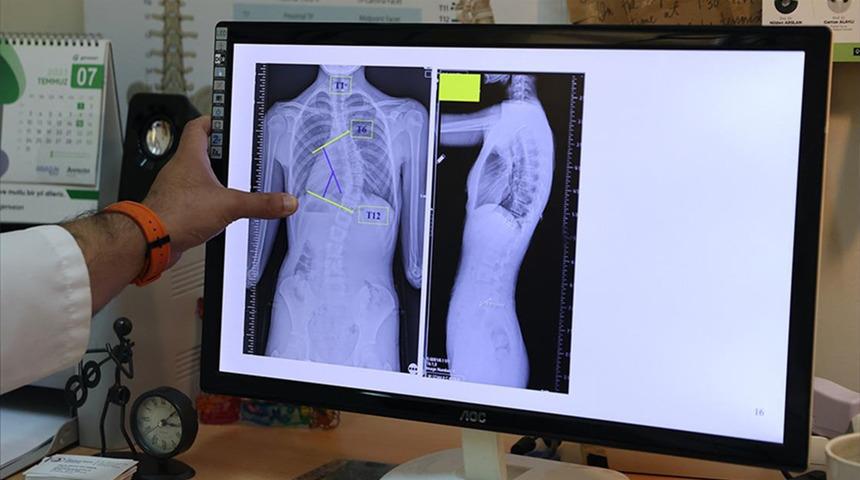

Erdem, tanı sürecine ilişkin de bilgiler vererek, "Skolyozun kesin tanısı ayakta çekilen bir röntgen filmiyle konur. Ancak öncesinde basit, hızlı ve etkili bir tarama yöntemi olan öne eğilme testini kullanıyoruz. Çocuk öne eğildiğinde kaburgalar veya bel bölgesindeki asimetri çok daha net şekilde görülür" şeklinde konuştu.

"Biz 10 dereceye kadar olan eğrilikleri skolyoz olarak değil, asimetri olarak kabul ediyoruz. 10 ila 20 derece arasındaki eğriliklerde çoğu zaman herhangi bir tedaviye gerek duyulmuyor ancak çocuğun yaşı ve büyüme potansiyeline bağlı olarak düzenli takip yapılması gerekiyor. 20 ila 40 derece arasındaki eğriliklerde ise egzersiz programları ve korse tedavileri ön plana çıkıyor. 40 derecenin üzerindeki eğriliklerde, çocuğun yaşı da göz önünde bulundurularak cerrahi tedavileri değerlendirmeye alıyoruz. Günümüzde 40 ila 50 derece arası bir gri zon olarak kabul ediliyor. Ancak 50 derecenin üzerindeki eğriliklerin mutlaka tedavi edilmesi gerekiyor."